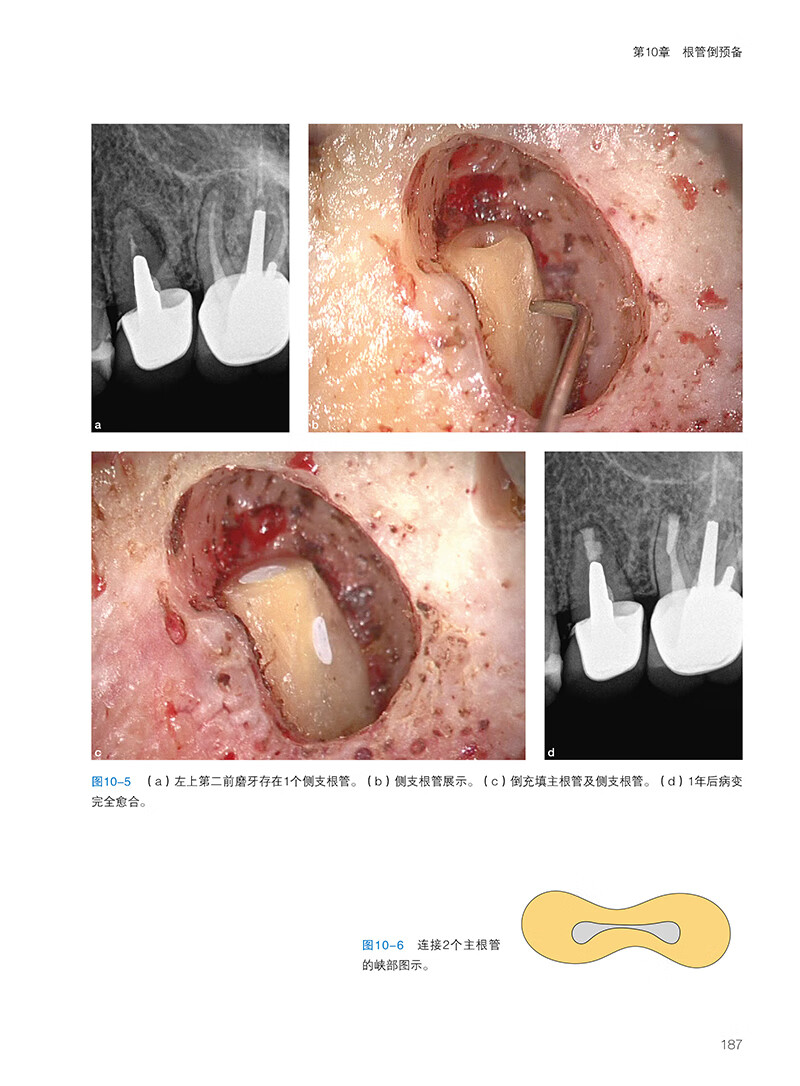

第8章非手術和手術性根管再治療

引言

非手術性根管再治療

根尖周病變

根管治療質量評估

遺漏根管及解剖特點

手術性根管再治療